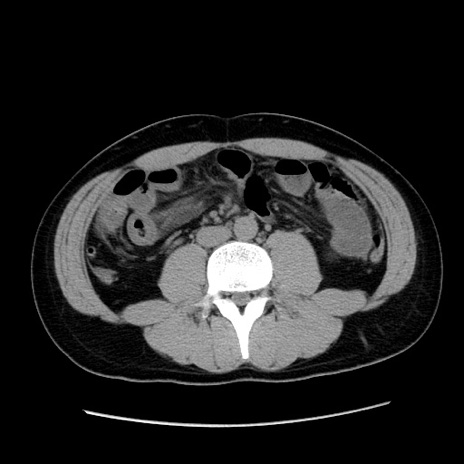

症例36(横断像)

【症例】20歳代 男性

【主訴】心窩部痛

【現病歴】今朝より上腹部痛あり。一旦軽快していたが再度出現したため救急要請。昨日夕に白身の魚を含む刺身を食べた。

【身体所見】BP 136/89mmHg、HR 74/min、BT 37.0℃、腹部:膨満、軟、心窩部に圧痛あり。反跳痛なし、筋性防御なし、腸雑音やや亢進あり。

【データ】WBC 17700、CRP 0.48